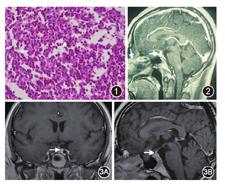

患者男,1995年2月出生。因"烦渴、多饮、多尿9个月,加重1个月余"于2014年7月29日入住复旦大学附属华山医院内分泌科。2013年10月(18岁)无明显诱因下出现烦渴、多饮、多尿,每日饮水量6 000~8 000 ml,排尿10余次,夜尿4~5次,每次约250 ml,尿色淡,一周后出现左侧胸部阵发性疼痛,偶有头痛,但无复视、视物模糊、皮疹、淋巴结肿大等其他症状。患者于当地医院胸X线片检查提示左侧肋骨病变。2014年2月外院行单光子发射计算机断层显像(SPECT)检查提示左侧第5肋骨病变,考虑为恶性骨肿瘤,行"左第5肋骨肿瘤切除+左肺上叶楔形切除术",病理考虑左第5肋骨"嗜酸性肉芽肿",累及周围软组织(图1)。术后患者自觉多尿症状缓解(自觉口干好转,尿量减少,夜尿减少至0~1次),未就嗜酸性肉芽肿和多尿进一步诊治。2014年6月多饮多尿症状再现并加重,伴乏力、双下肢酸痛和失眠。2014年7月外院垂体磁共振成像(MRI)增强提示垂体柄增粗(图2),结合多尿症状诊断为中枢性尿崩症,予弥凝(醋酸去氨加压素)0.1 mg/次,2次/d治疗,多饮多尿症状明显好转。为进一步明确诊断和后续治疗方案,患者于2014年7月入住我科。

体格检查:体温37.7 ℃,脉搏80次/min,呼吸14次/min,血压:115/67 mmHg(1 mmHg=0.133 kPa),颜面部及胸背部可及痤疮,无紫纹,未见皮下出血点,瘀点瘀斑;左侧肋下可见长约15 cm的陈旧性手术瘢痕;全身浅表淋巴结无肿大;腹部平坦,肝脾肋下未触及;双下肢无水肿。入院后辅助检查:血、尿和大便常规及肝肾功能正常,血糖正常,胸片和心电图未见异常。血钠146 mmol/L,血钾3.8 mmol/L,游离三碘甲状腺原氨酸4.88 pmol/L,游离甲状腺素12.85 pmol/L,促甲状腺激素3.36 mU/L,三碘甲状腺原氨酸1.76 nmol/L,甲状腺素113.30 nmol/L,晨血皮质醇417.36 nmol/L,促肾上腺皮质激素(ACTH)113.5 pmol/L,卵泡刺激素1.55 U/L,黄体生成素4.04 U/L,催乳素64.02 mU/L,睾酮12.80 nmol/L。血渗透压303 mOsm/kg·H2O(1 mOsm/kg·H2O=2.575 kPa),尿渗透压108 mOsm/kg·H2O。肿瘤标志物:正常范围。腹部B超未见肝脾肿大,浅表淋巴结B超检查发现双侧腋下少量肿大淋巴结。全身扁骨及长骨摄片未见异常。鞍区MRI增强:垂体高度正常,信号较均匀,增强后均匀强化,垂体柄下方结节状增粗,增强后结节状强化(图3)。正电子发射计算机断层成像(PET/CT):左侧第5肋骨病变治疗后,垂体柄稍饱满,未见脱氧葡萄糖(FDG)代谢异常增高,脑干FDG代谢欠均匀(未见异常增高灶);余PET显像未见FDG代谢异常增高灶。特殊检查:骨穿未见造血系统累及。

诊疗经过和预后:根据临床表现、实验室检查、影像学检查以及外院诊疗经过,弥凝治疗有效,功能诊断考虑中枢性尿崩症,垂体前叶各轴功能均正常。外院肋骨手术标本病理会诊:S-100(+),CD1α(+),langerin(+),CD68(-),LCA(-),Ki-67(+)(约30%),符合朗格汉斯组织细胞增生症(LCH)(图4)。病因诊断考虑为多系统LCH(累及垂体和肋骨)。治疗:继续弥凝片0.1 mg/次,2次/d控制尿量;原发病由血液科制定化疗方案。2014年8月11日起予以LCH-Ⅲ方案化疗1次[长春地辛4 mg(第1、8天)+地塞米松10 mg,1次/d(第1~8天)];2014年9月3日至10月17日给予长春地辛4 mg+醋酸泼尼松50 mg,1次/周,共5次;2014年10月29日至12月8日给予长春地辛4 mg(第1天)+醋酸泼尼松25 mg/次,2次/d(第1~3天),1次/周,共5次。患者减少并停用弥凝片,监测尿量维持2 000~3 000 ml/d。复查全身扁骨及长骨摄片未见明显异常,双侧颈部、锁骨上、腋下、腹股沟未见明显异常淋巴结肿大。垂体MRI平扫:垂体柄下方小结节,较前相仿,视交叉清晰(图5)。2014年12月11日至2015年9月25日继续给予长春地辛(第1天)+醋酸泼尼松25 mg/次,2次/d(第1~5天),每3周1次,共12次。治疗期间监测血糖、血脂、血压,未见异常,但体重增加15 kg。于2015年9月25日再次评估全身病情并未有复发情况。2016年1月行全身评估,三大常规、电解质、肝肾功能均在正常范围;垂体-甲状腺轴、肾上腺皮质轴、性腺轴评估均在正常范围;尿渗透压:557 mOsm/kg·H2O,尿量1 900 ml/d,腹部B超未见异常,全身扁骨及长骨X线片未见明显异常;查垂体MRI增强提示垂体柄结节状强化,病灶较前略有缩小(图6)。

本例患者因烦渴、多尿,同时伴有胸痛,切除左侧第5肋骨病变,病理会诊免疫组化S-100(+),CD1α(+),langerin(+),LCH诊断明确。LCH由朗格汉斯细胞克隆增殖形成(除了肺部原发性LCH),具体机制不明。既往将其归在炎症性病变中,由于半数研究样本中发现BRAFV600E基因突变,目前倾向于将其归为肿瘤增生性病变[6]。LCH常多器官累及,临床表现因累及器官的不同而不同[7]。最常累及骨骼(80%),其次是皮肤(33%)及垂体(25%),然后是血液系统(15%)、肺(15%)及淋巴结(5%~10%)[7]。25%的患者出现中枢性尿崩症,多系统累及患者中高达50%[8]。累及鞍区者MRI可表现为垂体柄增粗(>3 mm)、下丘脑占位等,根据影像学特点无法确诊,确诊依赖病理[9],膜表面S-100蛋白、Ki-67抗原、CD1α抗原、langerin抗原及膜结合的ATP酶等为确诊依据。本例患者尿崩症状同时鞍区MRI增强结果发现垂体柄下方结节状增粗,根据临床特点综合考虑垂体柄病灶为LCH。